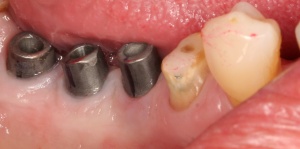

Bevor die Implantatprothetik angefertigt wird, sollten zahnärztlicherseits die periimplantären Weichgewebsverhältnisse erneut geprüft und bewertet werden. Sofern keratinisierte Gingiva periimplantär fehlt, sollte spätestens zu diesem Zeitpunkt ein weichgewebschirurgischer Eingriff (BGT, FST) erfolgen (Abb. 6).

Bevor die Implantatprothetik inseriert wird, überprüft der versorgende Zahnarzt, ob die periimplantären Strukturen sondiert und insbesondere durch den Patienten gepflegt werden können. Dies lässt sich bereits auf dem Meistermodell nach Abnahme der Silikonzahnfleischmaske kontrollieren. Die Krone sollte idealerweise dem Emergenzprofil des Implantates oder des Abutments folgen (Abb. 7a/b).